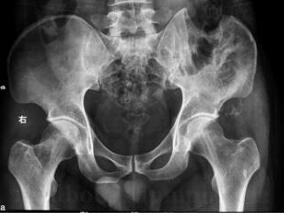

1小时条评论30岁男性,左髂骨软骨肉瘤术后竟两次复发!如5年首次治疗前行术前活检病理得到软骨肉瘤的结果,首次手术就应行广泛切除。当时情况行内半骨盆Ⅰ区、Ⅱ区切除,保留肢体是可行的。3年前肿瘤复发后,仍只将髂骨外软组织肿块切除,未行广泛的外科手术,致使肿瘤继续生长...